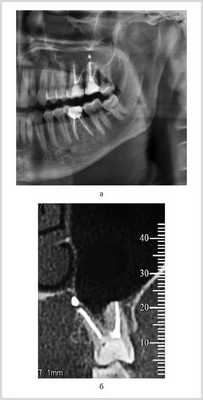

ОПМГ достоверно передавали взаимоотношение выведенного из КК пломбировочного материала с корнями зубов и анатомическими деталями зубочелюстных сегментов. В большинстве случаев отображение пломбировочного материала в проекции дна верхнечелюстных пазух или нижнечелюстного канала не позволяло определить, находится пломбировочный материал вне или внутри этих анатомических образований. В подобной ситуации данные КЛКТ приобретали решающее значение (рис. 7, а, б).

Рис. 7. Исследование области зуба 2.7 и дна верхнечелюстной пазухи слева. а — на фрагменте ОПМГ в проекции дна верхнечелюстной пазухи виден пломбировочный материал, выведенный из корня 2.7; создается ложное впечатление о проникновении пломбировочного материала в пазуху; б — на косом срезе КЛКТ пломбировочный материал, выведенный из небного корня зуба 2.7, располагается вне пазухи, у ее внутренней стенки.